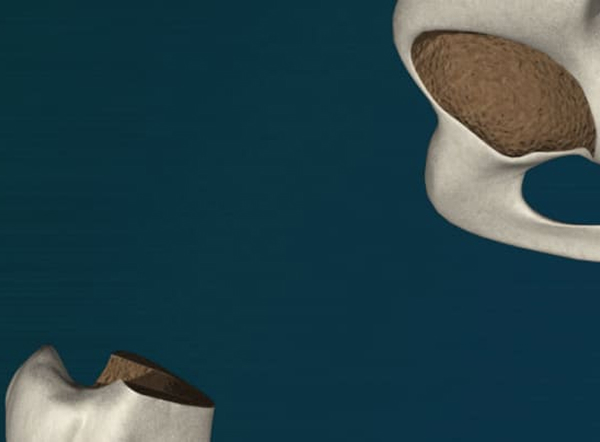

股関節の場合

手術は股関節のやや後方、または外側、あるいは前方の皮膚を切開して行います。

• 骨頭を切除し、大腿骨の内側を整えます。

• ロボティックアームを用いて骨盤(臼蓋)の表面を整えます。